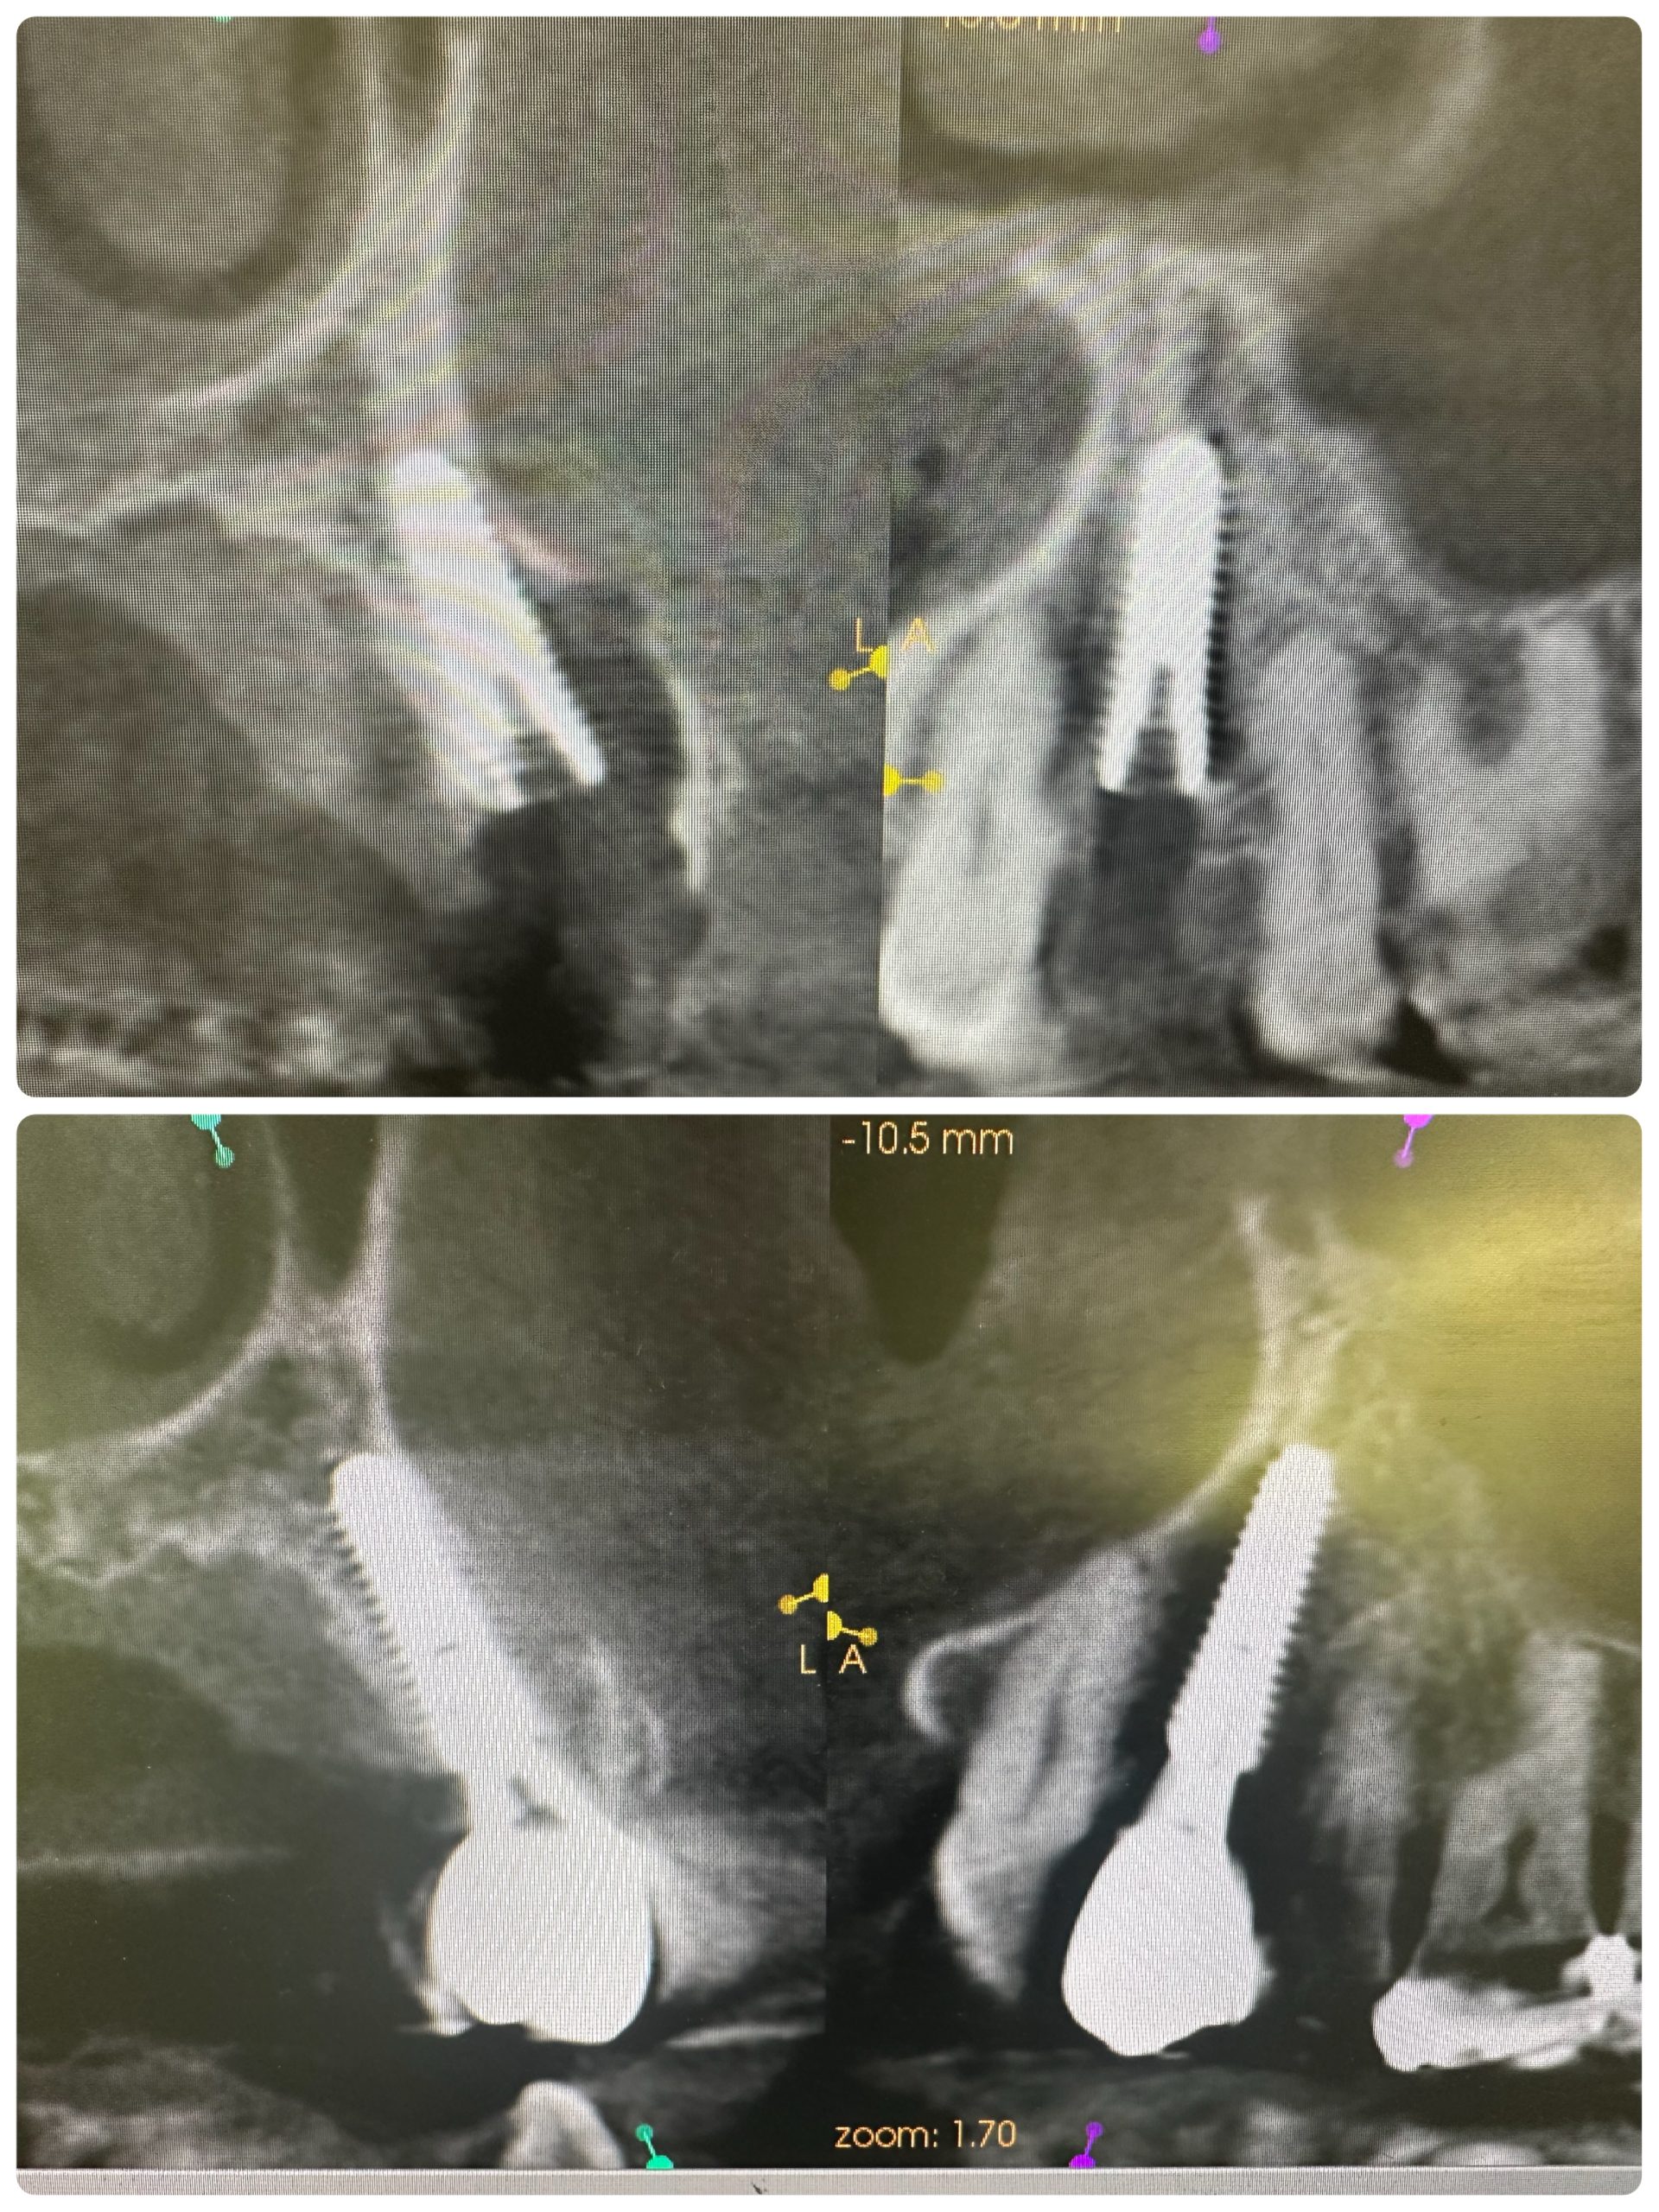

次のお方は、本年4月に抜歯即時、ソケットシールド

セミルーナフラップした方の頬側の骨再生画像確認

ソケットシールドしてるから、吸収なくボリーュミー